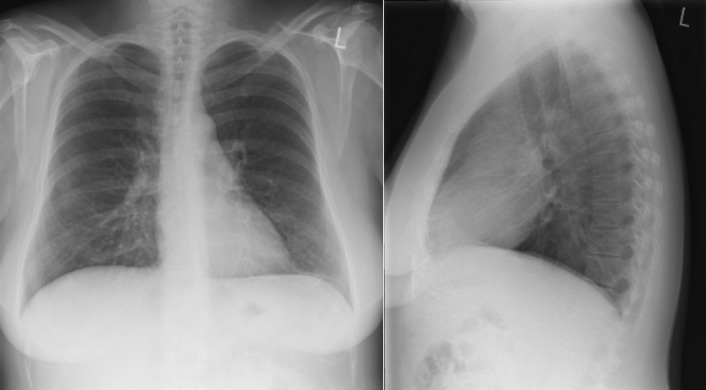

Enlargement of the left atrium is present in the majority of cases of hypertrophic cardiomyopathy ( Figs 14-1 to 14-4 ). Left atrial enlargement is greater in patients with hypertrophic cardiomyopathy when there is concurrent mitral insufficiency. The degree of left ventricular enlargement is variable but is usually mild and consistent with left ventricular hypertrophy. About 50% of cases have cardiomegaly, usually mild to moderate. Mitral annular calcification is common.